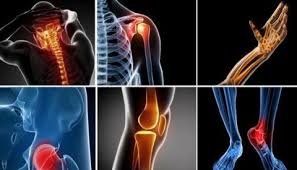

Persistent joint, bone, or musculoskeletal discomfort can significantly affect daily life, making simple activities such as walking, climbing stairs, or lifting objects painful and challenging. For patients experiencing these issues, finding the best ortho doctor in Pune is a crucial step toward restoring mobility, reducing pain, and improving quality of life. Expert orthopedic care goes beyond temporary symptom relief; it addresses the root cause of discomfort while supporting long-term function, stability, and joint health.

The best orthopedic doctors address a wide spectrum of musculoskeletal problems, including:

- Chronic joint pain and degenerative arthritis

- Knee and hip injuries or preservation

- Fractures and post-traumatic complications

- Ligament and tendon injuries from sports or accidents

- Spinal alignment issues affecting mobility

- Cartilage damage and joint instability